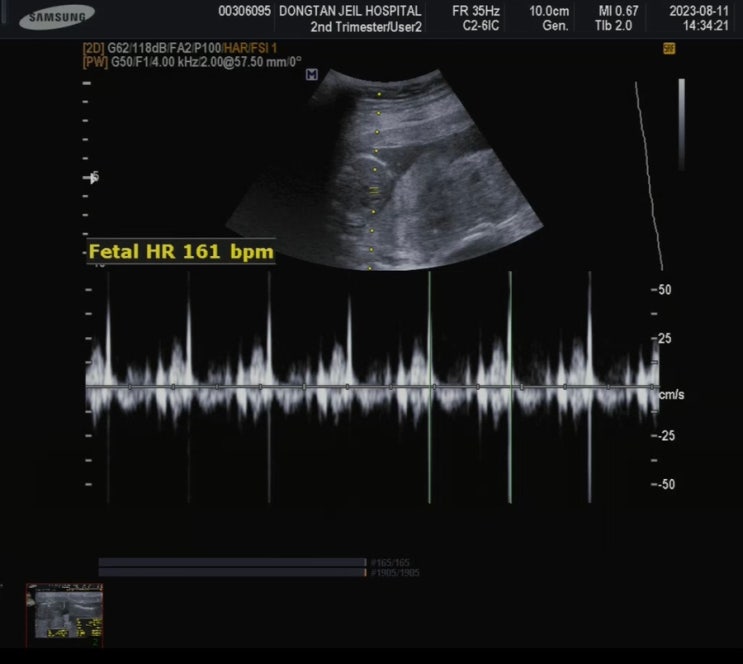

자궁경부무력증 임신 24주차 우동이 기록 정밀초음파 실패

첫째인 우주가 자궁경부무력증으로 아주 큰일날뻔 했던 이력이 있어서 둘째 우동이 임신 후에는 바로 동탄...

동탄제일병원 자궁경부무력증 예방맥수술 후 첫진료 / 우동이 성별

첫째때 자궁경부무력증으로 24주때 양막 돌출, 응급맥 수술을 했지만 다행히 38주에 정상 분만하긴 했어요!...